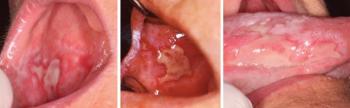

A papularis és reticularis forma akár tünetmentes is lehet, bár ez ritkán fordul elő, mert a lichenes betegeknek erős betegségtudata van (pszichés háttér). A hám ezeknél a betegeknél hyperorto- vagy hyperparakeratoticus. Nincs hámatrophia és fekélyesedés (11.2. ábra). A jellemző klinikai kép: fehér csíkok a szájnyálkahártyán, mely faág, szarvasagancs vagy anularis (gyűrűszerű) reticularis rajzolatot mutat. Ez az összefolyt papulák képe, az ún. Wickham-féle striák (11.3. ábra).

A papulák vonalas rajzolat helyett gyakran szorosan, egymás mellett nagyobb összefüggő felületen alakulnak ki plakkszerű elváltozás alkotva (11.4. ábra), amely leukoplakiára emlékeztet és differenciáldiagnosztikai problémát okozhat. A betegség folyamán a léziók morfológiája változhat, valamint változhat a betegség kiterjedése és intenzitása is. Általában a klinikai tünetek nem súlyosak és gyakran a beteg csak a nem teljesen sima felszínt veszi észre.

11.5. ábra. Lichen oris – bullosus forma

Az ún. simplex lichen (papularis, reticularis, plakkos) mellett az orális lichen csoportba változatos klinikai képet mutató, ún. exsudativ lichen típusok is tartoznak. Ezekben az elsődleges lézió sokszor a bullaképződés, amely felszakadva erózióba, majd a zavart gyógyulása során atrophiás formába mehet át. Azonban erózios lichen kialakulhat bullaképződés nélkül is. A bullosus lichen ritka betegség, sokszor benignus mucosus pemphigoiddal együtt fordul elő, azonban a jellegzetes Wickham-striák a lézió körül mindig felfedezhető. Ilyenkor hám-kötőszövet határán a sejtrétegek egymástól elválnak és gyulladásos exsudatum jelenik meg (11.5. ábra).

11.6. ábra. Lichen oris – atrophiás forma

11.7. ábra. Lichen oris – eróziós forma

A bulla azonban hamarosan felszakad és erózióba megy át. Ez gyakran jelentős fájdalommal társul. Erózió azonban kialakulhat hólyagképződés nélkül is. A lichen atrophiás formájában a szájnyálkahártya atrophiás változáson esik át, basalis rétege gyenge és oedemás (11.6. ábra). Ez a nyálkahártya-felszínen fekélyképződésben manifesztálódhat, és a szomszédos nyálkahártya- területeken reticularis elváltozás látható. Kezdetben az atrophiás hám nagyon törékeny és gyorsan széteshet, ami jellegzetes eróziós elváltozást okoz (11.7. ábra). Az irodalom, elsősorban az angolszász szakkönyvekben, a hámvesztésnél az erozív és az ulceratív kifejezést szinonímaként használja. Az a terminológia, melyet ennek a betegség formának a leírására az orális medicina használ, félrevezető lehet, mert nem tükrözi a szövettani jellegzetességeket. Ez a hám felületes hiánya, amely súlyosabb egyéb komplikáló faktorok nélkül nem terjed a kötőszövetre, és nem jár kötőszövet necrosissal, tehát valójában nem ulcus, hanem erózió. Az általunk használt erozív kifejezés a szájnyálkahártya szabálytalan (felületes vagy mély) károsodásának leírása, amit sárgásfehér, fibrines lepedék borít.

Az atrophiás formában (11.6. ábra) a hám elvékonyodik, és mint erythaemás nyálkahártyaelváltozás jelenik meg. Mind az erozív, mind az atrophiás forma a szájban tüneteket (fájdalom) okoz. A betegség reticularis és plakkos formájában az ilyen tünetek ritkák (bár a betegnek panaszai vannak), különösen fűszeres vagy csípős ételek fogyasztásakor. A nyálkahártya érzékeny mechanikus irritációkra. Az első tünete, amit a beteg észlel, az a fogsor okozta trauma, mely más klinikai tüneteknél korábban jelenik meg. Különösen időskorban lehet nagy buccalis vagy nyelven lévő fekély, ezek fájdalmasak. Az ilyen fájdalmas elváltozások zavarják a beteget az étkezésben és a beszédben.